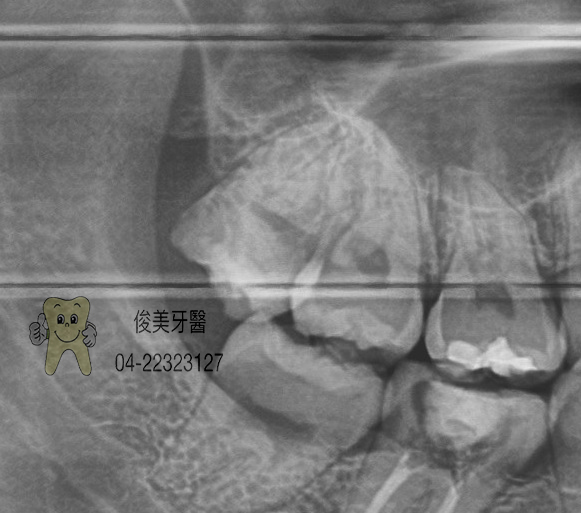

智齒拔除案例15

患者於門診中表示,牙縫很會塞東西,牙齒不舒服,醫師檢查後居現患者口內空間不足,智齒長歪且不容易清潔,

因此建議患者拔除,患者立刻決定拔除。

順利取出後,讓患者非常訝異,原來這麼輕鬆.........

但明明都有刷牙,牙齒却.....

因担心傷口癒合慢,所以在傷口置入幫助癒合的止血膠原。

患者傷口癒合正常。